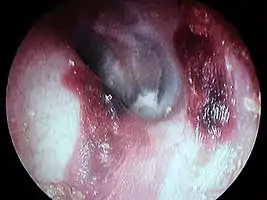

Hématome du conduit auditif externe gauche post coton tige

- Hématome